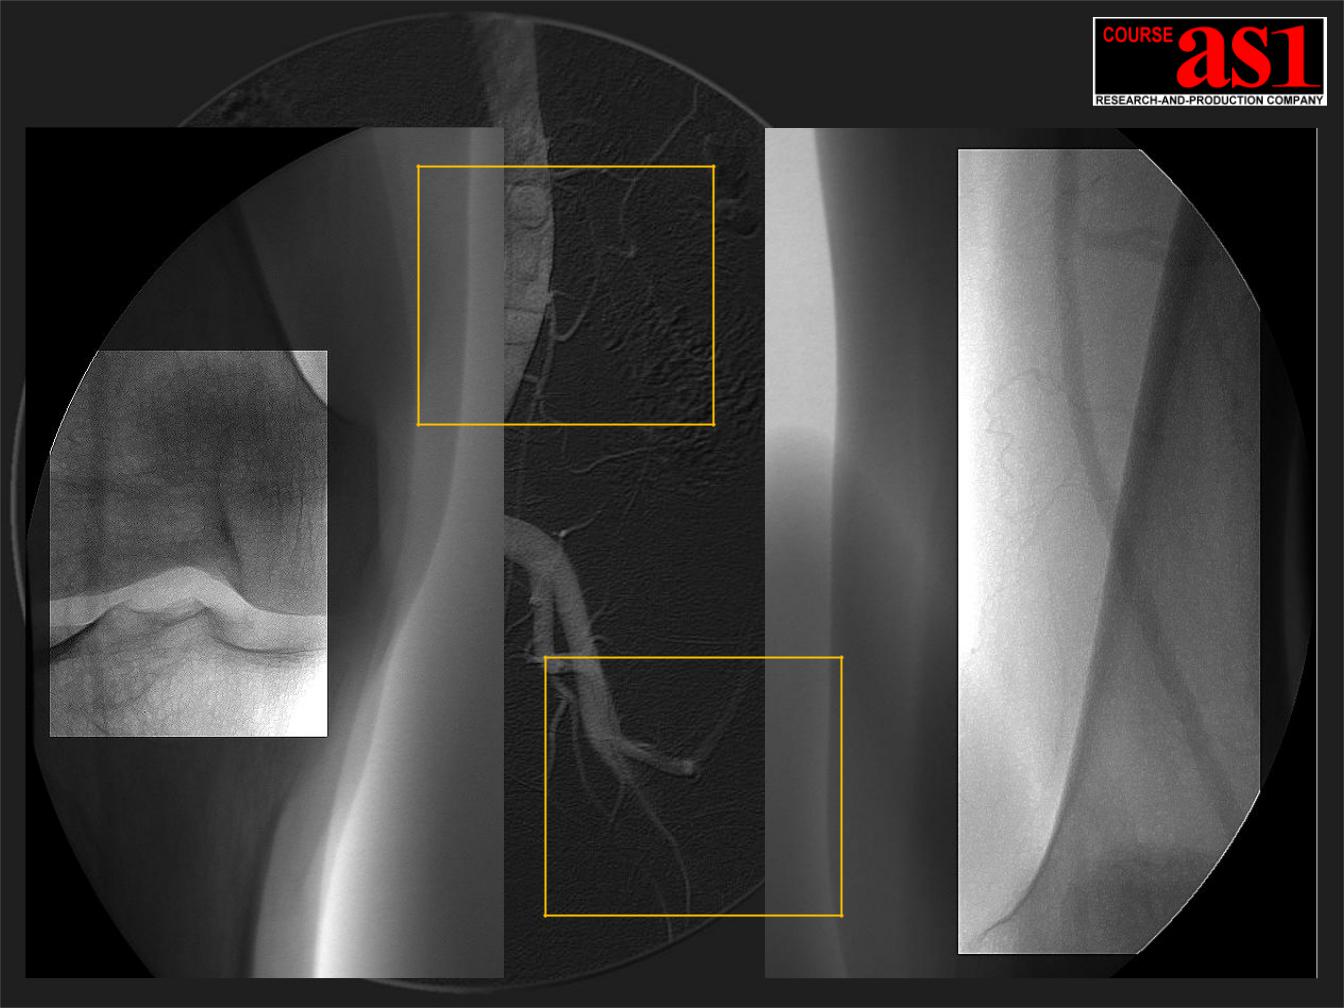

Зонная 2D Обработка 12-ти битной ангиографической серии В выделенной зоне интереса хорошо виден слабый контраст

Слева

Очень слабый след рентгеновского контраста просматривается на фоне мощного коленного сустава.

Справа

Слабый контраст хорошо виден на фоне как мягкой ткани, так и на фоне плотной

трубчатой кости.